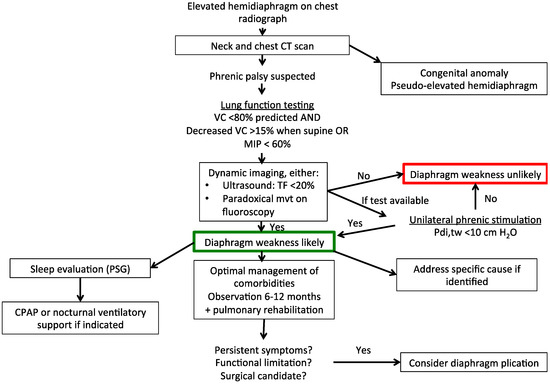

Smoking is the primary cause of emphysema which makes it a preventable illness. Diaphragm weakness due to medical intervention most commonly occurs as a result of physical trauma to the phrenic nerves or diaphragm muscle. Surgical treatment is an option for more advanced cases or if breathing becomes so impacted daily life is affected.

You may not need any treatment. Depending on the severity of injury to the diaphragm some doctors recommend non-surgical options to treat the breathing issues associated with diaphragm weakness and paralysis.

Place one hand on your abdomen and breathe deeply. Reduced number of alveoli air sacs required for normal breathing. In severe cases when there is no simple treatment that can relieve dyspnea your doctor may prescribe morphine. Congenital diaphragmatic hernia CDH. There is usually a long history of heavy smoking. Shortness of breath may be accompanied by wheezing. Diaphragmatic dysfunction caused by transverse myelitis or leukemic infiltration of the cervical spinal cord in a patient with leukemia and shortness of breath. To treat phrenic nerve irritation This condition can be managed with a breathing pacemaker which takes over the responsibility of sending messages to the diaphragm. The cause for shortness of breath was thought primarily due to stable angina on tread mill test positive finding but Chilaiditis syndrome should also be considered as a cause for the shortness of breath.

The rise in intraabdominal pressure further increases intrathoracic and lung volume by pushing the lower rib cage outward. In severe cases when there is no simple treatment that can relieve dyspnea your doctor may prescribe morphine. Diaphragmatic dysfunction caused by transverse myelitis or leukemic infiltration of the cervical spinal cord in a patient with leukemia and shortness of breath. Diaphragmatic plication a surgical procedure that pulls the diaphragm down by introducing a repeated series of continuous sutures across the diaphragm and pulling the muscle taut. A bedside fan or open window with a breeze are also simple but very effective treatments to lessen dyspnea. Depending on the severity of injury to the diaphragm some doctors recommend non-surgical options to treat the breathing issues associated with diaphragm weakness and paralysis. P E Pulmonary embolism.